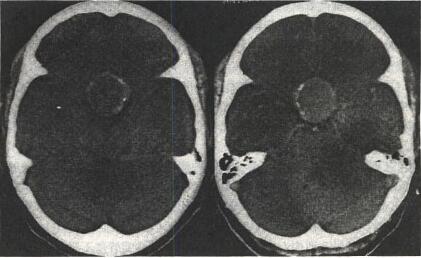

高血压性脑出血概述

脑出血(cerebral hemorrhage)是指非外伤性脑实质内血管破裂引起的出血,占全部脑卒中的20%~30%,急性期病死率为30%~40%。发生的原因主......